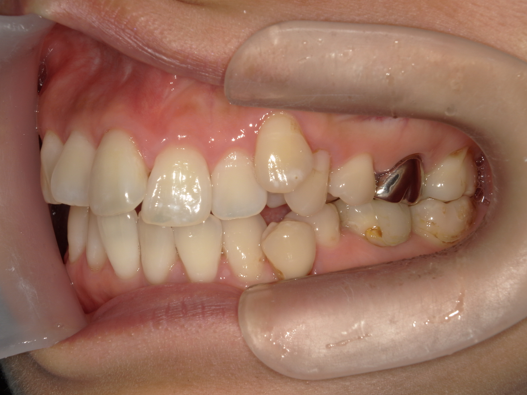

症例2:八重歯が気になる

| 患者様データ | 20代 女性 |

| 来院主訴 | 八重歯が気になる。 |

| 治療内容 | 八重歯を治すために上の親知らずを抜歯し、インビザラインにてマウスピース矯正を開始しました。かみ合わせを整えるためにゴムかけを行いました。 |

| 概算治療費 | 約85万円 |

| 治療期間 | 1年3ヶ月 |

| 通院回数 | 8回 |